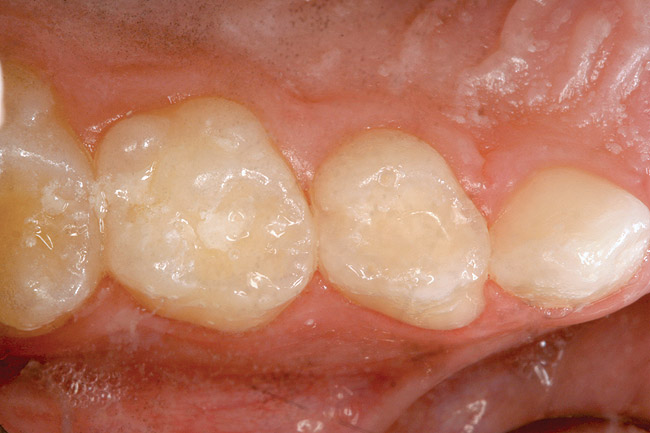

Figure 5  Preoperative photograph of tooth A.

Figure 5